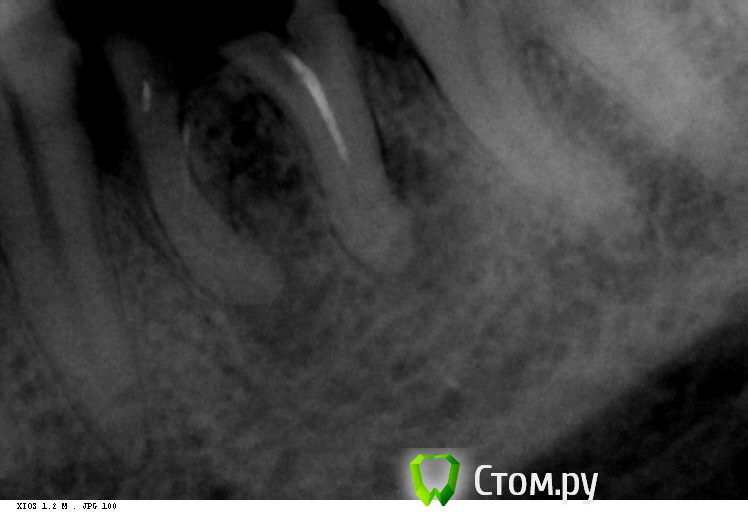

shishok Опубликовано 6 декабря, 2013 Поделиться Опубликовано 6 декабря, 2013 На шестом корни отдельно друг от друга-абсолютное показание к удалению. 1 Ссылка на комментарий

govorov Опубликовано 6 декабря, 2013 Автор Поделиться Опубликовано 6 декабря, 2013 Так я предполагаю, что болят только соседние, а 6-й чёрный (или красный), но не болит, никому не мешает и как-то жуёт и, поэтому, удалять его НЕ нужно! Может такое быть?Чем плохи «корни отдельно друг от друга»? Они, наверно, несколько лет уже так (не меньше года). Там где делали снимки, сказали, что видели что-то плохое на корнях 6-го, типа, «кисту с гноем». Действительно там видно такое? Если видно, то лечится только удалением? Ссылка на комментарий

DmitrySH Опубликовано 6 декабря, 2013 Поделиться Опубликовано 6 декабря, 2013 (изменено) Вокруг корней 6-го зуба достаточно большие очаги воспаления. Зачем хранить в себе очаг инфекции? IvanK, опередил Изменено 6 декабря, 2013 пользователем dmitrySH 1 Ссылка на комментарий

IvanK Опубликовано 7 декабря, 2013 Поделиться Опубликовано 7 декабря, 2013 Это действительно видно на снимках? да есть ли такая необходимость (удалять) есть если такая возможность есть. такой возможности нет Если возможности лечить нет и надо удалять, то привели убедительные аргументы за это. Вам уже все ответили, далее обсуждать тему бессмысленно.Как будет панорамный снимок - пишите, открою тему Ссылка на комментарий